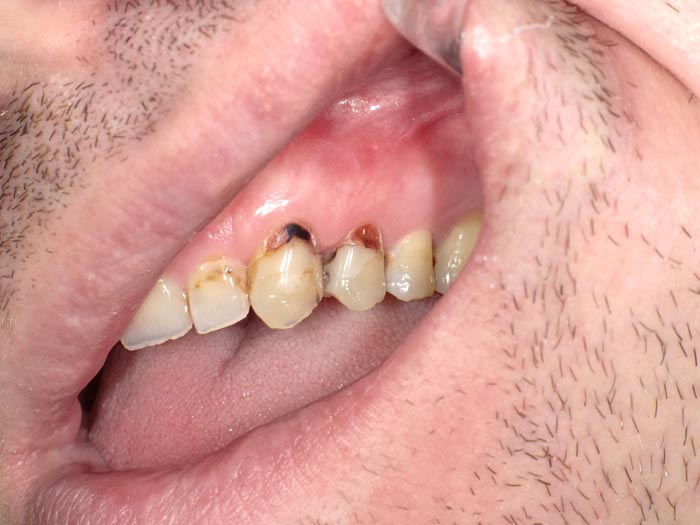

Case 1

A 37-year-old patient presented for treatment after years of neglect. After administering anesthetic and placing an Isolite isolation device, we prepared teeth #10–12 and restored them

with Activa Bioactive-Restorative composite.